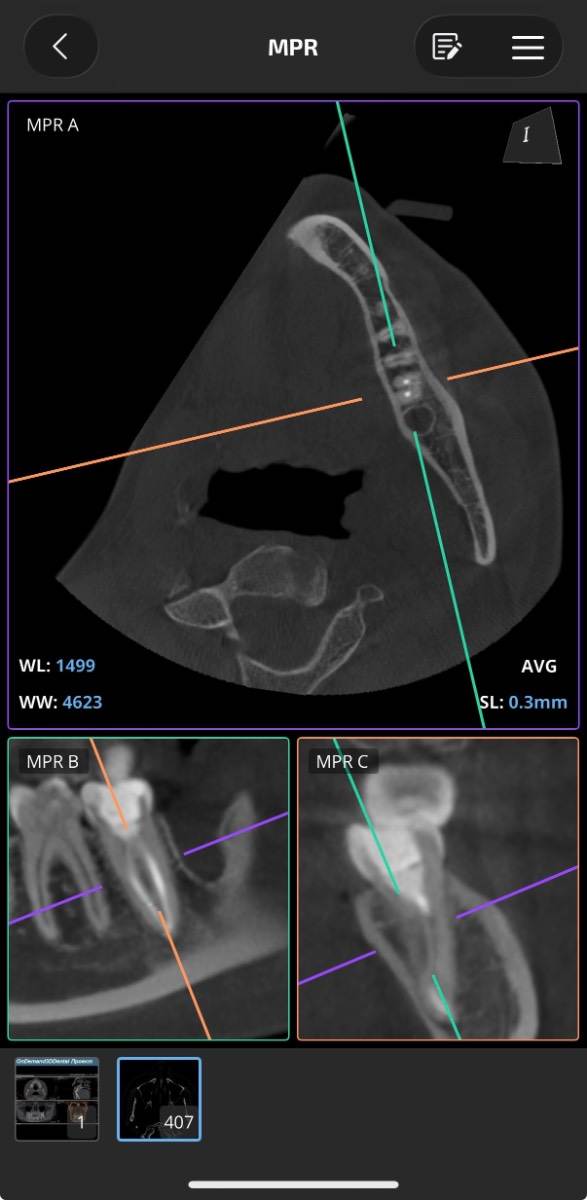

Добрый день, пожалуйста объясните что с зубом простыми словами, я если честно ничего не понял, там проблемы? Просто к стоматологу пойду через неделю только чтобы мне объяснили КТ, хочется сейчас узнать хоть что-то: 16 зуб эндодонтически лечен. Коронковая часть восстановлена рентгеноконтрастным материалом. Небный корень: канал широкий, обтурирован высококонтрастным материалом, верхушка корня не закрыта. Периапикально очаг деструкции костной ткани 4,5х4мм. запломбирован. Щёчно-медиальный корень – признаки дилацерации корня, канал запломбирован частично. Периапикально очаг деструкции 4х4мм Щёчно-дистальный корень: длина корня не более 4мм, в канале и за верхушкой корня определяется пломбировочный материал. Периапикально признаки деструкции костной ткани, очаг с нечеткими контурами. Жалоб на зуб вроде нет.. просто если очень долго вообще не жевать ничего или вообще челюстью не работать, при надкусывании чувствуется дискомфорт, но очень очень быстро проходит и больше не появляется